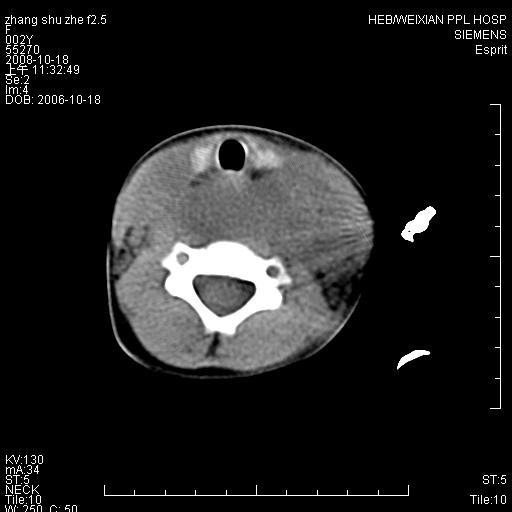

以下是引用dyqct在2009-2-10 21:04:00的发言:[br]年龄?性别?有发烧吗?[br]鼻咽部、口咽部、喉咽部及颈椎前间隙广泛肿厚,明显占位效应并致相应组织变形。ct值22-28hu。[br]考虑:1、颈前脓肿可能性大;[br] 2、建议增强或治疗后复查。

以下是引用jiangjing在2009-2-11 11:37:00的发言:[br]急性病程,鼻咽部、口咽部、喉咽部及颈椎前间隙广泛肿厚,明显占位效应并致相应组织变形.考虑颈部感染性病变(脓肿?);建议行进一步检查。